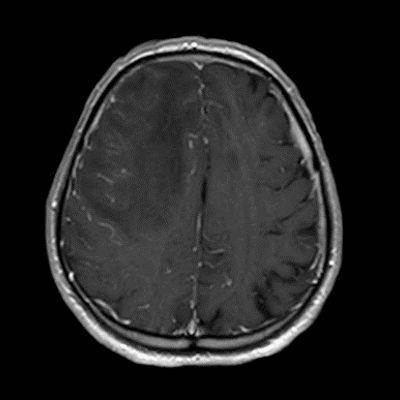

- A) Aksiyel planda FLAIR sekansta asimetrik kortiko-subkortikal vazojenik ödemi düşündüren yüksek sinyalli hafif ekspansil lezyonlar (turuncu ok).

- D) Kontrastlı T1A sekansta hafif leptomeningeal boyanma (sarı ok).